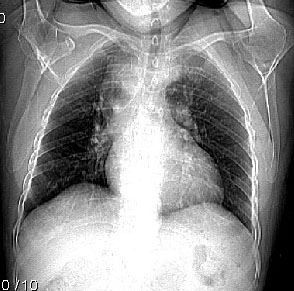

患者,女因为我吐血,{经过临床以好转}平片高度怀疑上纵隔增宽,纵隔旁型肺癌?{两次未见明显变化}有问题行ct.

先天发育异常:降主动脉位右侧,主动脉弓形态欠规整。余未见异常影像。

主a弓及降主a都位于右侧,近膈肌时位于椎体前,,左室流出道及其他结构未见明显异常

右位主动脉弓伴迷走左锁骨下动脉。

楼主发布的是右主动脉弓的由中动脉弓并迷走左锁骨下动脉,并不是5楼战友说的全反位。